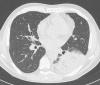

Results: According to RT-PCR results, 152 patients were COVID-19 negative (48%) and 162 were COVID-19 positive (52%). We found substantial agreement between RT-PCR results and CT findings (p < 0.000001), as well as an almost perfect agreement between the two readers. Mixed GGO and consolidation pattern with peripheral and bilateral distribution, multifocal or diffuse abnormalities localized in both upper lung and lower lung, in association with interlobular septal thickening, bronchial wall thickening and air bronchogram, showed higher frequency in COVID-positive patients. We also found a significant correlation between CT findings and patient's oxygenation status expressed by PaO2/FIO2 ratio.